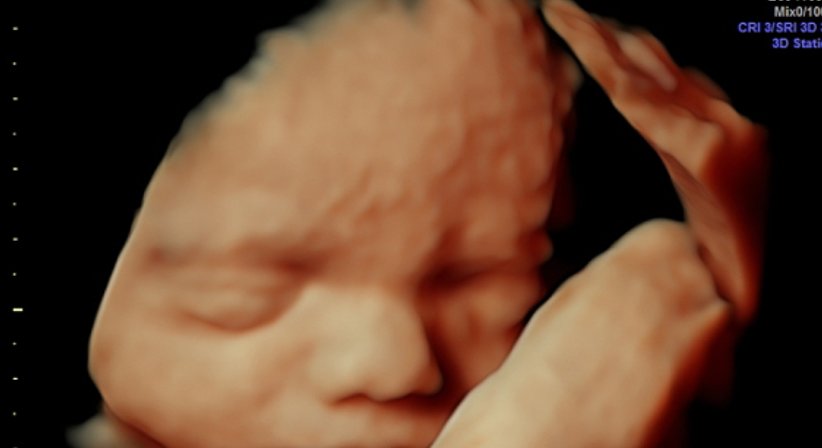

3D/4D Ultraschall

Bei meinen Patientinnen wird bei guter Kindslage auf Wunsch auch ein 3D Bild angefertigt.

Aus Termingründen ist es mir NICHT möglich für "ordinationsfremde" Patientinnen diese Untersuchung anzubieten!